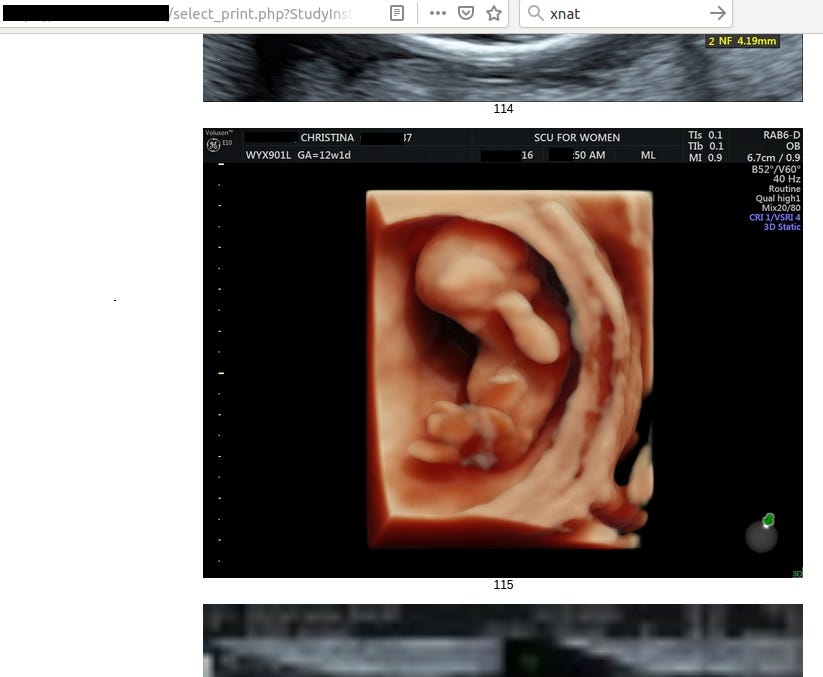

In this case leak contained 4,5 TB of data including radiology photos of pregnancies with diagnosis (almost 2M images!), invoices or personal patient’s data.

Going back to the main topic and the most important data in the leak, each patient has from 10 up to 40 radiology photos with description.

Frankly speaking, it says nothing for me but for someone acquainted with the topic it’s trove of information about health of patient and her fetus.